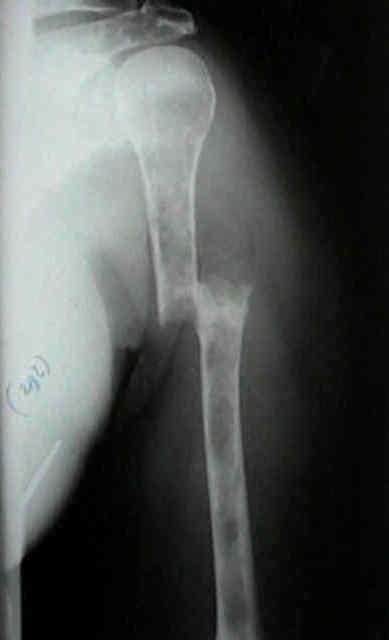

Se localiza, preferentemente, en los huesos donde existe médula ósea roja: vértebras, costillas, esternón, pelvis, cráneo y huesos largos (tercio proximal fémur y húmero).

Las fracturas patológicas de columna o fémur pueden ser el primer

síntoma. Se producen con un traumatismo mínimo o incluso sin trauma.

Radiográficos:

Las radiografías normales pueden mostrar osteopenia difusa.

"Lesiones perforadas" o en "sacabocado" sin ninguna formación de nuevo-hueso circundante. Su diámetro es variable (hasta 5 cm.), redondas y múltiples.

Con el tiempo las lesiones pueden cambiar de osteopenia difusa a más permeativa con patrón destructivo apolillado, y a veces con expansión cortical.

La destrucción del hueso ocurre con poca o ninguna formación de hueso reactivo a menos que haya una fractura patológica.

Los mielomas pueden presentarse como lesión solitaria o más normalmente como un tumor difuso, involucrando múltiples huesos, incluyendo vértebras, cráneo, pelvis y fémures.